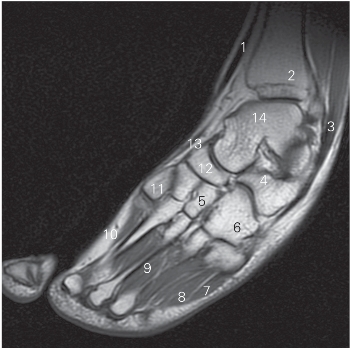

图5-60 经第一跖骨的足冠状断层MR T1加权图像

1 胫骨 tibia 2

长屈肌 flexor hallucis longus

3 距骨 talus 4 跟骨 calcaneus

5

长屈肌腱 tendon of flexor hallucis longus

6 足底方肌 quadratus plantae 7 小趾展肌 abductor digiti minimi

8 趾短屈肌 flexor digitorum brevis 9 足底肌 sole muscle

10 第一跖骨 1st metatarsal bone 11 内侧楔骨 medial cuneiform bone

12 舟骨 navicular bone

图5-61 经内侧楔骨的足冠状断层MR T1加权图像

1 胫骨 tibia 2 距骨 talus

3 胫骨前肌 tibialis anterior 4 舟骨 navicular bone

5 跟骨 calcaneal 6 骰骨 cuboid bone

7 腓骨长肌 peroneus longus 8 小趾展肌 abductor digiti minimi

9

趾 great toe 10 足底肌 sole muscle

11 第一跖骨 1st metatarsal bone

12

长伸肌腱tendon of extensor hallucis longus

13 内侧楔骨 medial cuneiform bone